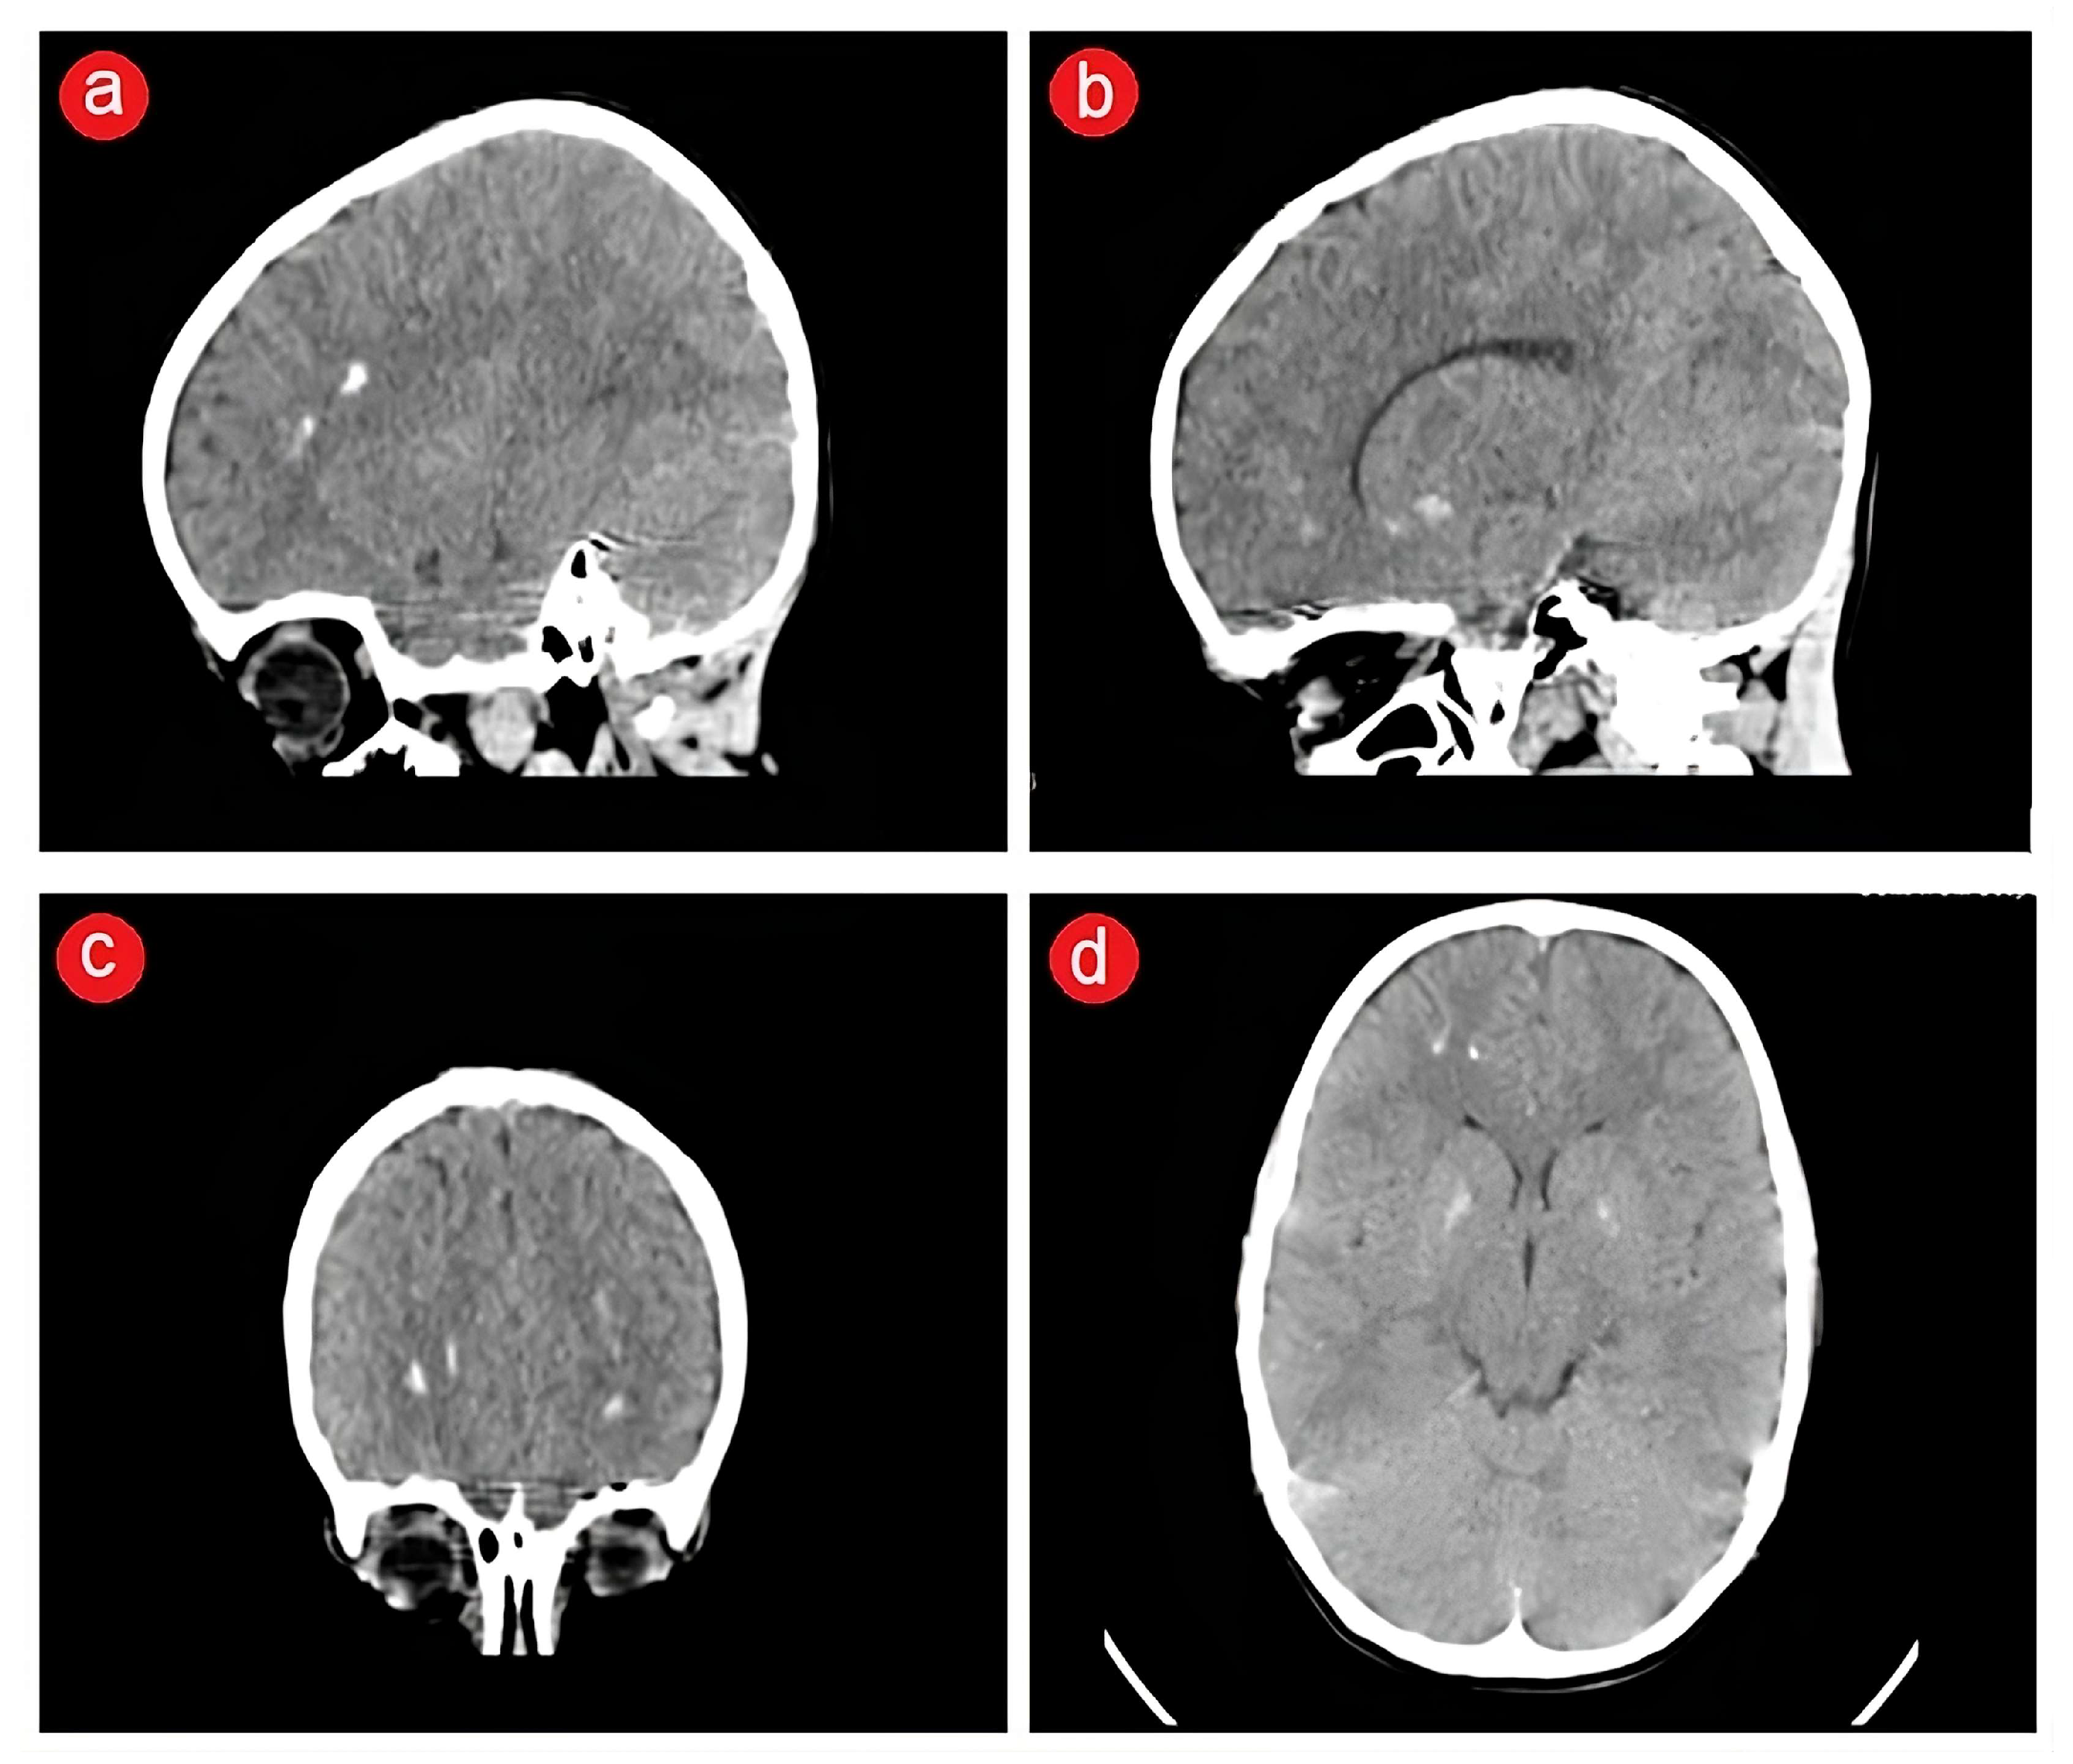

2.3. Biological and Paraclinical Assessment